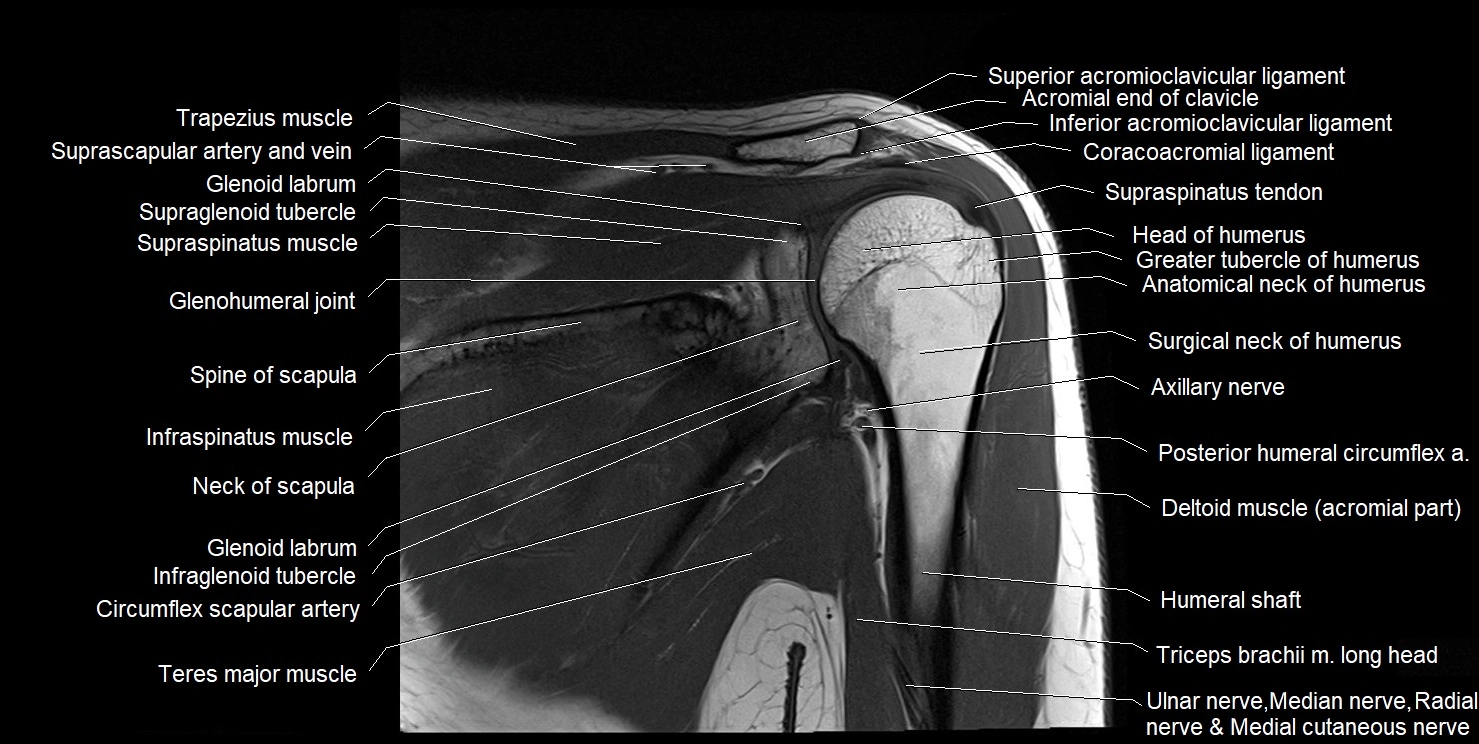

MRI images

image